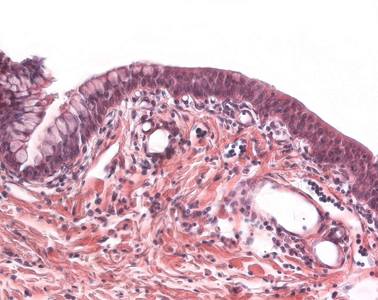

Präparat 99: Augenlid, H.-E.

Die Wimpern (Cilien) an der Lidkante können quer oder längs getroffen sein. Die Talgdrüsen, die in die Haartrichter der Cilien einmünden, werden im Lid als Zeis-Drüsen bezeichnet, obwohl sie sich histologisch nicht von Talgdrüsen anderer Haare unterscheiden. Die Meibomschen Drüsen (Glandulae tarsales) hingegen sind holokrine Talgdrüsen, die nicht mit Haarwurzeln vergesellschaftet sind. Die Azini der Meibomschen Drüsen liegen nahe der Lidhinterseite in einer bindegewebigen Platte (dem Tarsus des Lids) und besitzen Ausführungsgänge, die von einem mehrschichtigen isoprismatischen Epithel ausgekleidet sind und an der hinteren Lidkante münden. In ihnen auftretende Retentionszysten und Entzündungen führen zu den Hagelkörnern (Chalazia).

Glandula tarsalis

(Meibomsche Drüsen) größte Drüsen der Augenlider; sie befinden sich im Flechtwerk des Bindegewebes der Lidplatten, sind nicht mit den Wimpern assoziiert und münden mit ihren Ausführungsgängen nah der hinteren Lidkante. Das durch holokrine Sekretion abgegebene Sekret enthält viele Lipide, die wesentlich dazu beitragen, dass die Tränenflüssigkeit nicht über den Lidrand läuft.

Chalazia

(Hagelkörner) erbsengroße, an den Augenlidern lokalisierte Granulome, die durch Sekretstauung nach Verschluß der Ausführungsgänge, durch Entzündungen, Tumore oder spontan von den Glandulae tarsales (Meibom-Drüsen) ausgehen.